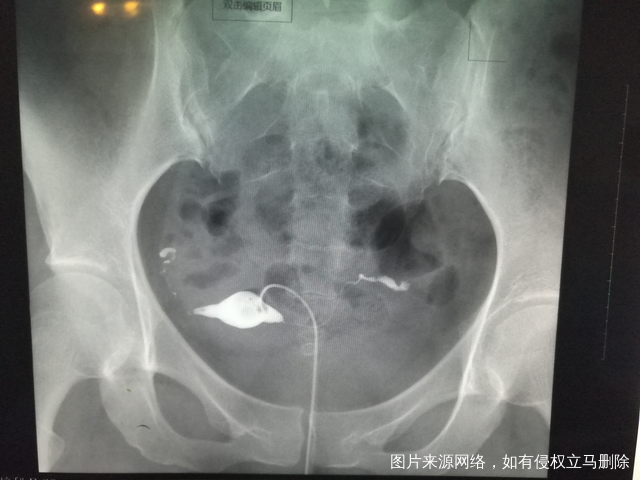

做完输卵管造影第六天了小腹还是感觉沉甸甸的如

可以热敷腹部,如果有发热,腹痛加剧,白带量多,有异味,随时就医